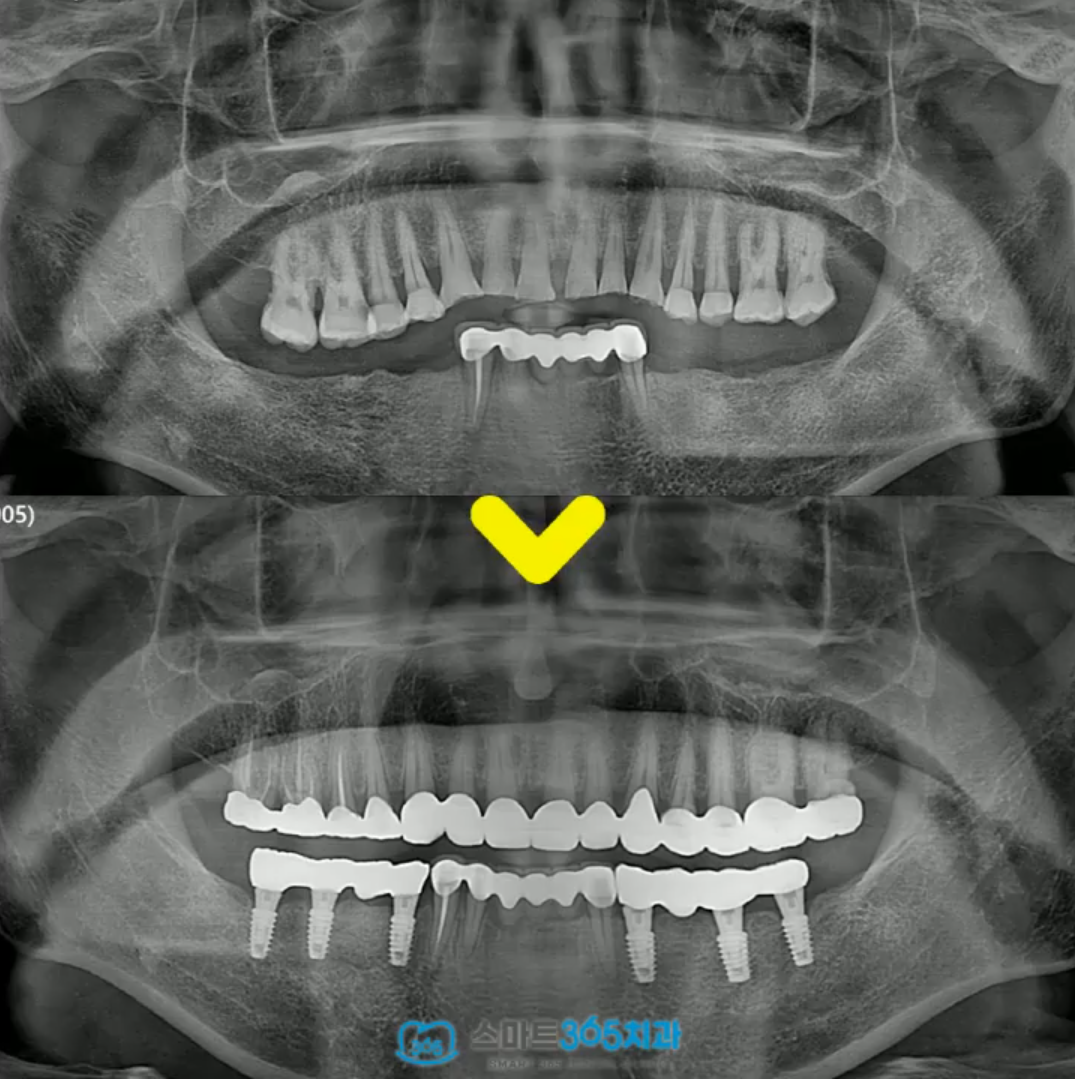

오늘은 마모되고 정출된 치아를

보철 수복과 임플란트를 통해서 교합 재건했던

사례를 이야기 나누어볼까 합니다 😊

내원하셨던 환자분의

파노라마 방사선사진입니다. ^^

아래 어금니를 상실한 후 오래 방치하여

위 어금니가 내려와 교합이 무너진 상태로

내원해 주셨는데요..!

어금니 교합이 무너져서 앞니만 교합되다 보니

앞니는 교모가 심해서 크라운으로 수복하기로

결정하였습니다^^

하악 임플란트 식립 후,

보철을 올리면서 정출된 어금니도 깎아

크라운을 씌우며 천천히 임시치아 쓰면서 적응 후,

조금씩 교합을 올려 교합을 맞추기로 했습니다.

이렇게 교합을 올리는 것을

“교합 거상”이라고 부릅니다 ^^